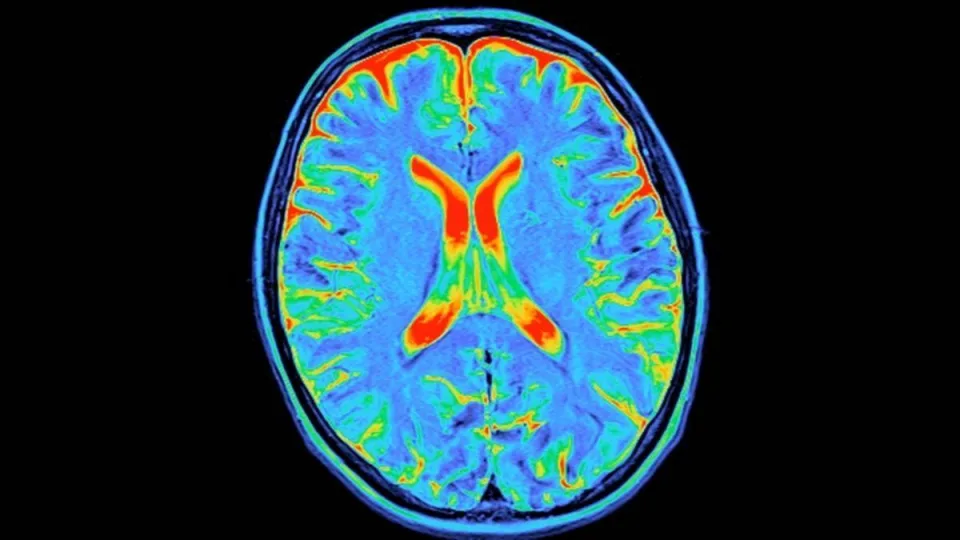

Keturi protinio gyvenimo lūžiai: atskleista, ką su jūsų smegenimis daro 9, 32, 66 ir 83 metų ribos

Žmogaus smegenys nėra kietai užprogramuota mašina. Tai lankstus organas, kuris visą gyvenimą keičiasi ir persitvarko, prisitaikydamas prie mūsų patirčių bei amžiaus. Naujas didelio masto tyrimas rodo, kad šie pokyčiai vyksta ne tolygiai, o per aiškiai atpažįstamus etapus.

Jungtinės Karalystės „University of Cambridge“ ir Jungtinių Valstijų „University of Pittsburgh“ neuromokslininkai nustatė keturis didelius smegenų jungčių lūžius tarp gimimo ir senatvės. Kiekvienas jų žymi savotišką naują smegenų gyvenimo skyrių.

Kaip sakė tyrimo bendraautoris Duncan Astle, daugeliui žmonių gyvenimas atrodo suskirstytas į fazes, ir pasirodo, kad smegenys gyvena panašiai. Tyrėjai išanalizavo 3 802 sveikų žmonių nuo kūdikystės iki 90 metų magnetinio rezonanso duomenis.

Pagal smegenų struktūrinių jungčių pokyčius jie išskyrė keturias amžiaus ribas, ties kuriomis keičiasi bendras smegenų „laidų“ kryptingumas. Šie taškai yra apie 9, 32, 66 ir 83 gyvenimo metus. Jie apibrėžia penkias dideles epochas, tai vaikystę, paauglystę, suaugusiojo laikotarpį, ankstyvą senėjimą ir vėlyvą senėjimą.